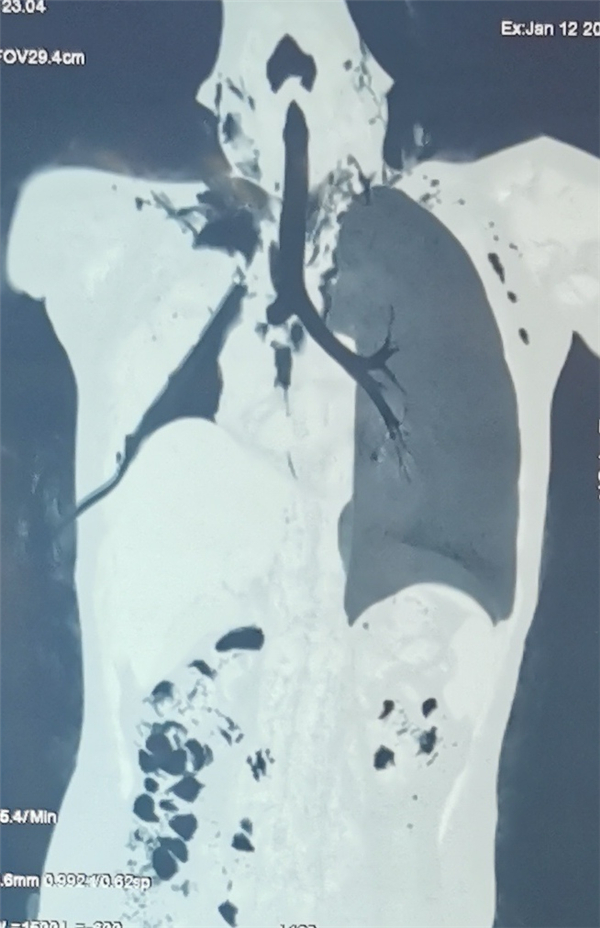

心胸外科戚家峰主任憑着豐富的臨床經驗,考慮患兒這次的「皮外傷」可能直接損傷了氣管,但這樣的閉合性外傷損傷氣管的病例在臨床中實屬罕見。為了進一步明確診斷,為患兒進行肺CT及氣道重建影像檢查,仔細分析後得出的結果仍然支持氣管「撕裂」甚至「斷裂」的可能,決定手術胸腔探查,查明原因。麻醉後為了保證手術順利進行和綜合評估,打贏這場硬仗,請耳鼻喉科高源主任使用硬質氣管鏡探查右主支氣管情況。

戚家峰主任採用胸腔鏡進胸就發現患兒右側主支氣管在距離隆突(氣管分叉)約1cm處完全斷裂,斷面呈爆破樣,滿視野都是游離碎裂的氣管軟骨,整個右肺已完全「掉落」在胸腔內,失去了原有的功能。同時發現孩子破裂的氣管形成短路,大量氧氣隨破裂的氣管外漏,血氧急劇下降僅為35%。在危急時刻,麻手科主任楊狄主任將氣管插管下入左側支氣管,真正實現了左單肺機械通氣,患兒呼吸狀況得到好轉並防止右側胸腔的血不能倒流到左側肺內,保證良好的通氣和生命體徵。戚家峰主任繼續為患兒進行了游離右肺及縱隔胸膜、修補氣管斷面、修補肺臟、吻合支氣管及成形等一系列高難度操作,手術歷時近5個小時。